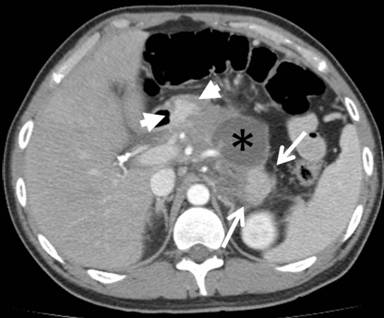

After necrosectomy, drains are laid in and around the necrosectomy bed, and these may be placed to suction and may be on occasion be used for postoperative lavage. Following both necrosectomy percutaneous drainage, a controlled pancreatic fistula may result, but will generally close with nonoperative management, such as the SEALANTS approach, as described above [57]. In cases of DDS (Figure 2), the orphaned pancreatic tail must be provided with a new route to the gastrointestinal tract. In these cases the transgastric approach is an especially attractive route for debridement, as a durable operative cystogastrostomy between the posterior wall of the stomach and the rind of the WON provides this route. When open debridement is better approached elsewhere, such as via the transverse mesocolon, then pancreaticoenteric continuity may be re-established via a cystojejunostomy. Depending on the nutritional tolerance of the patient, some form of feeding tube may be indicated at the time of open necrosectomy.

|

Figure 2. CT image showing walled-off necrosis (WON) causing pancreatic-duct disruption (PDD). A young, otherwise healthy male with moderately severe acute alcoholic pancreatitis developed an acute necrotic collection (ANC) in the mid-body of the pancreas that matured into WON (asterisk) over the subsequent month. The patient had recurrent symptoms and failure to thrive due to failure of the secretions from the viable pancreatic tail (arrows) to traverse the area of pancreatic necrosis (asterisk) to reach the viable pancreatic head (solid arrowheads). Percutaneous and endoscopic efforts failed, and he underwent successful open debridement, with a Roux-en-Y cystojejunostomy. After an uncomplicated recovery, he is well nearly 2 years later. |